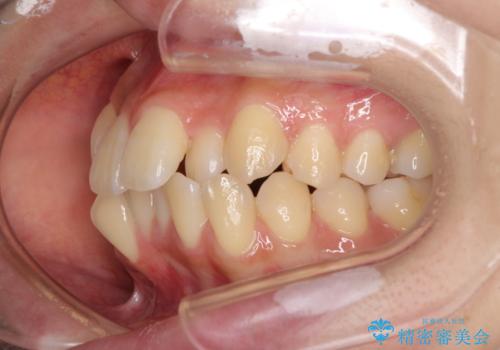

- 前歯のデコボコやクロスバイトと上顎の前突感による口の閉じにくさを気にして来院された患者様です。

目立たない装置を希望されたので、上顎が裏側装置のハーフリンガルを選択し、上下左右の小臼歯(計4歯)を抜歯して矯正治療を行うこととしました。

表側のワイヤー矯正に比べると治療期間は長く、費用も高額となりますが、どうしても目立たせたくないという方にはお勧めの抜歯矯正です。